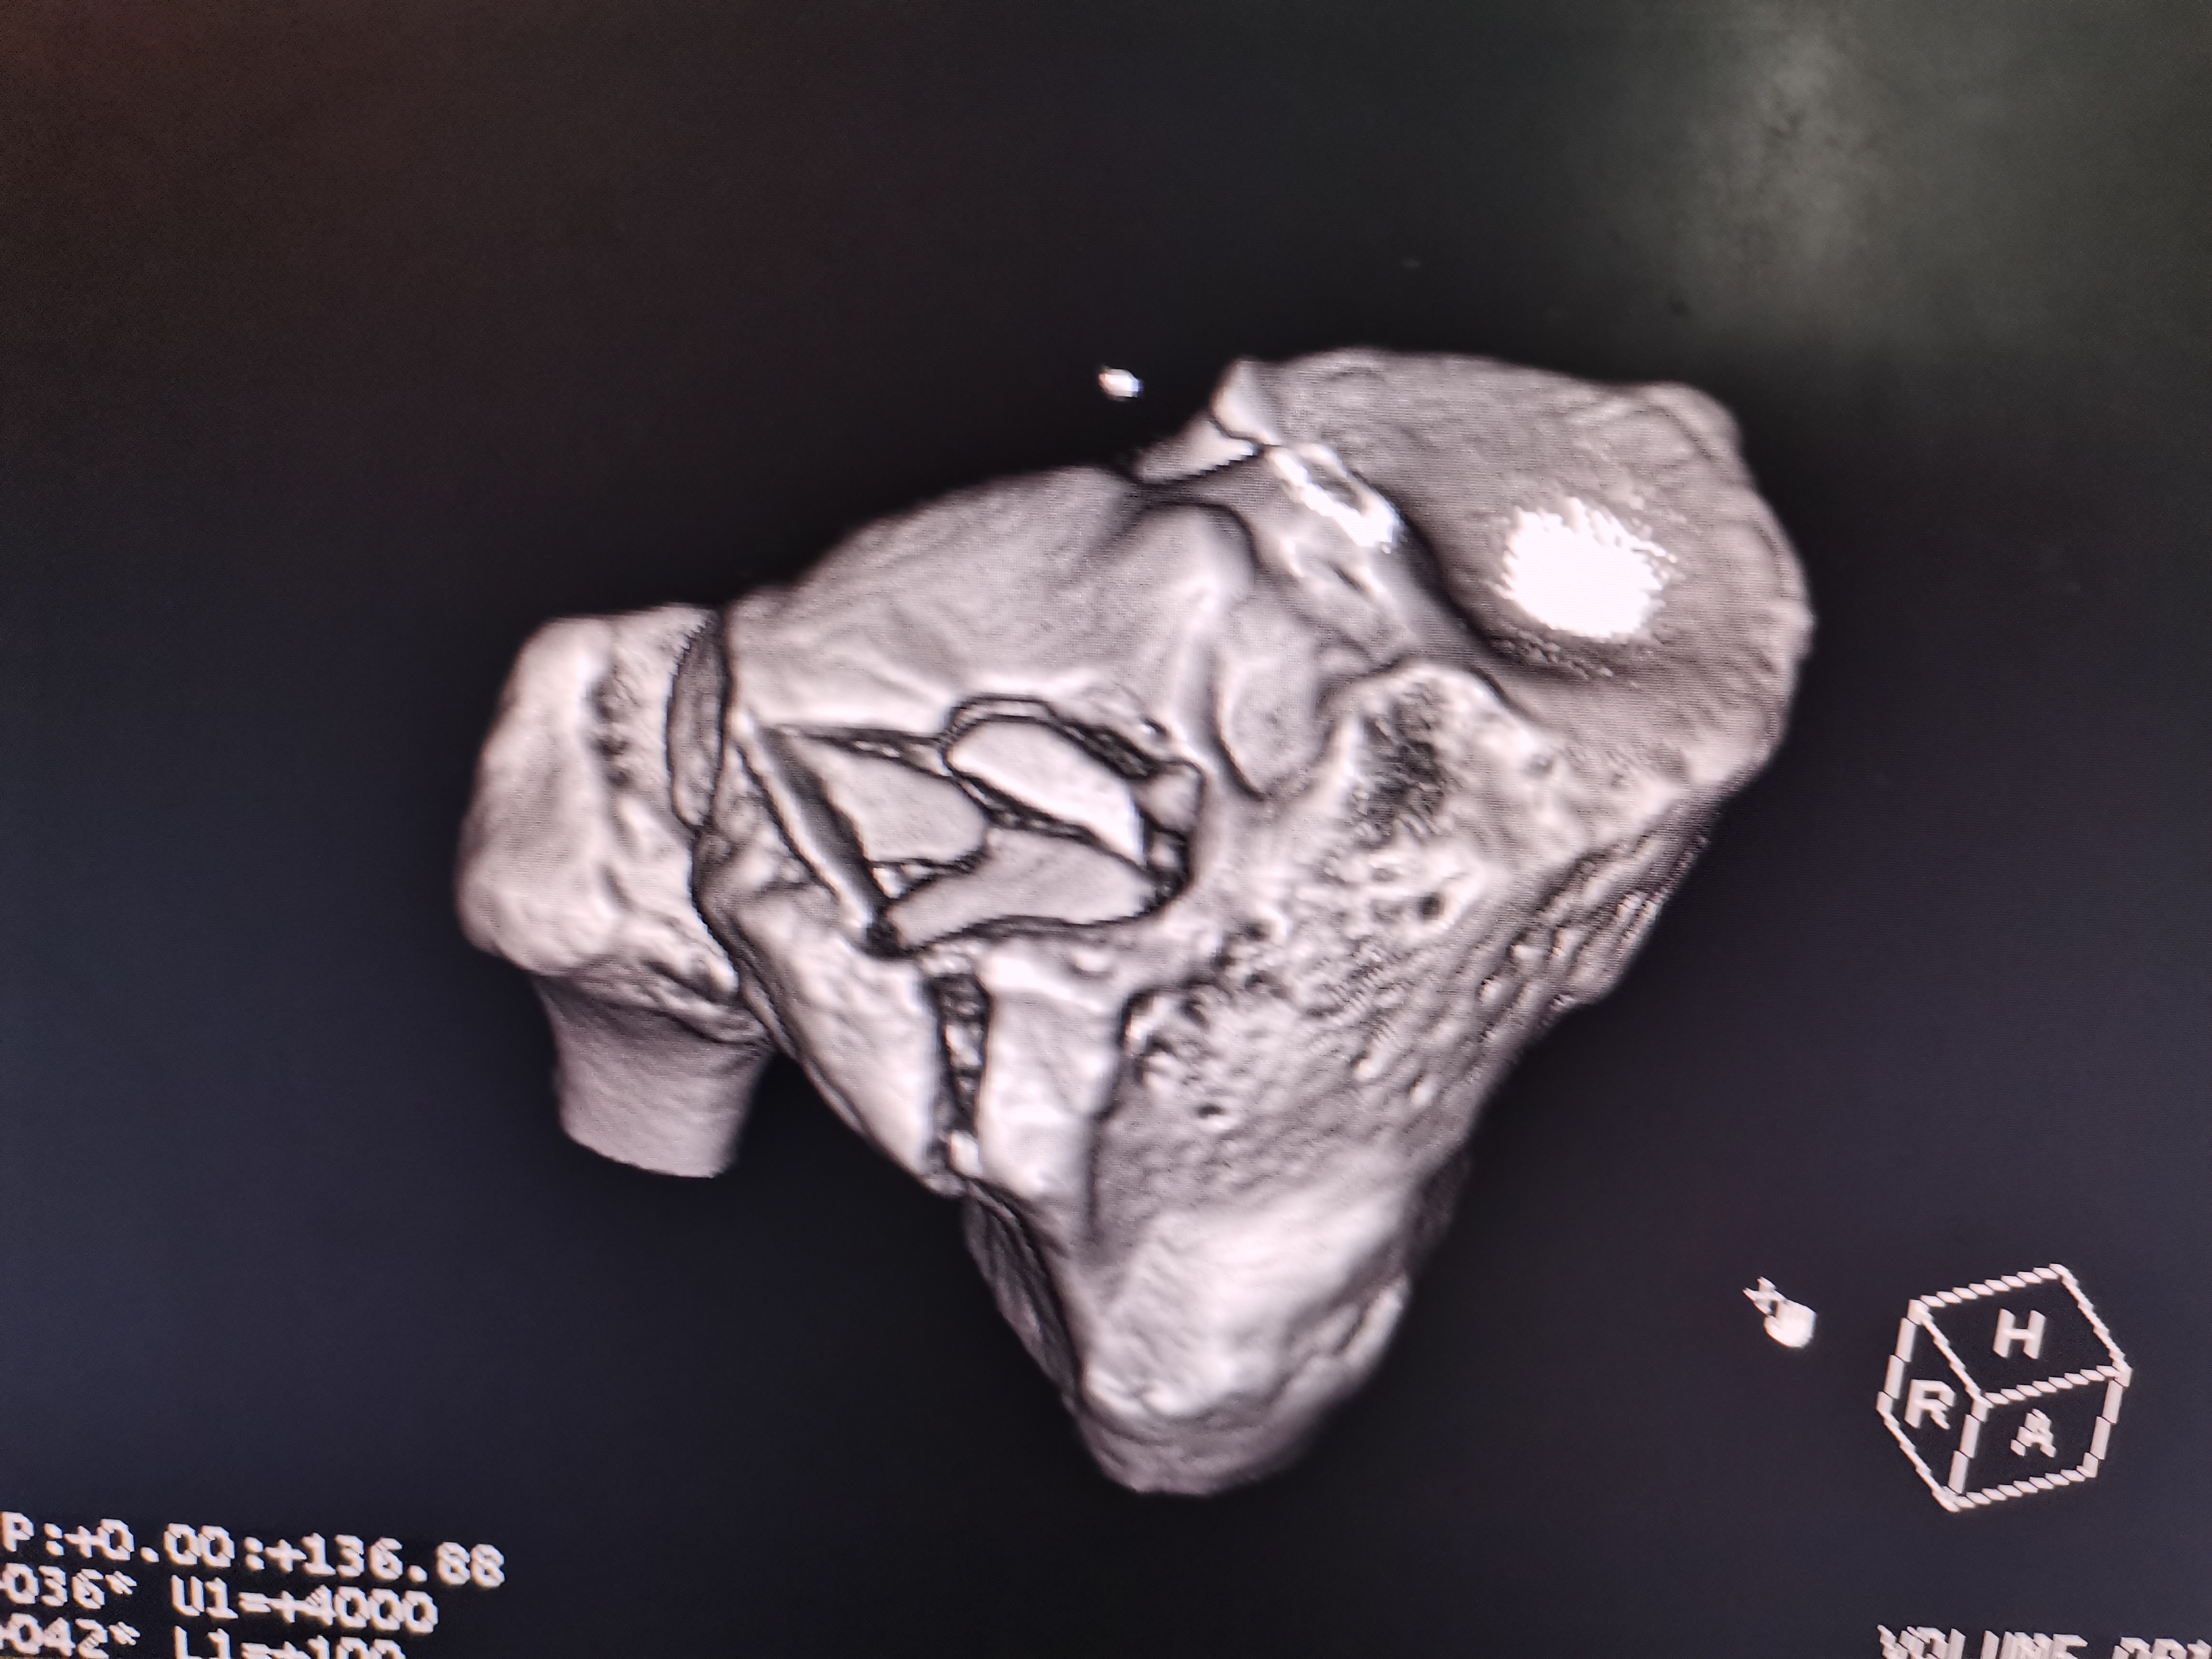

- CT(计算机断层扫描):必查项目,通过三维重建可清晰显示关节面塌陷程度、骨折块数量及移位情况,为分型和手术方案制定提供关键依据。

- Ⅴ型:内外侧平台双髁骨折(高能量创伤,软组织损伤重)。

- Ⅵ型:双髁骨折+干骺端-骨干分离(最严重类型,伴严重软组织损伤、骨缺损,并发症多)。